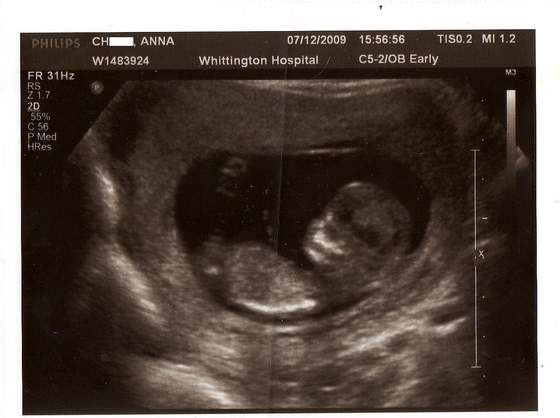

cudne maleństwa